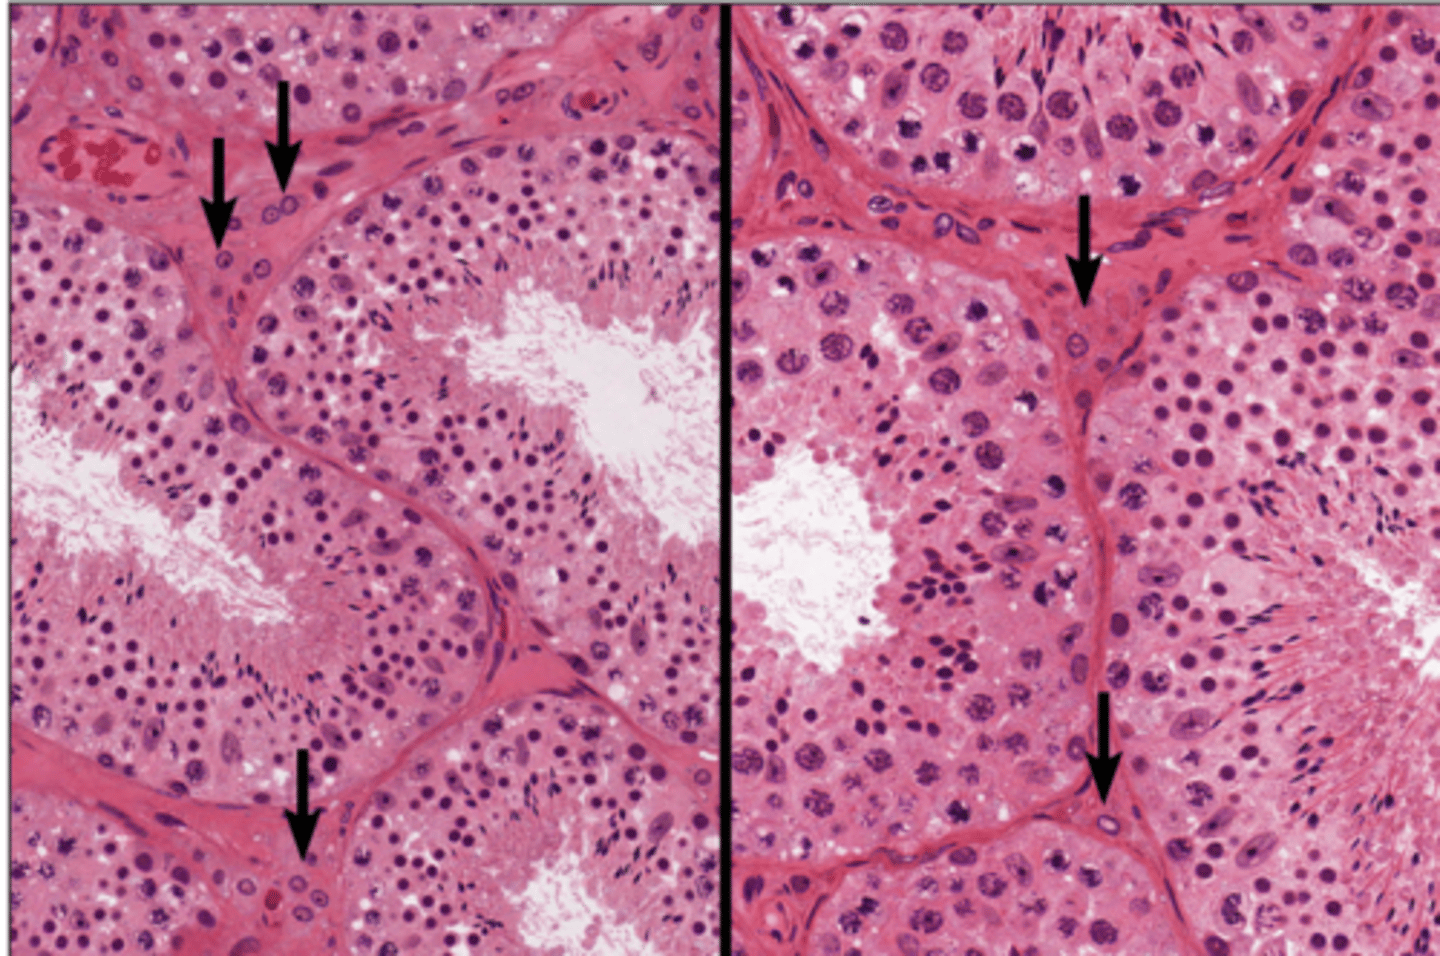

Spermatogenesis

Spermatogenesis

Spermatogonia

Primary spermatocyte

Spermatogonia

Spermatid (early)

Primary spermatocyte

Spermatid (late)

Spermatid (early)

Spermatozoon

Spermatid (late)

Spermatozoa